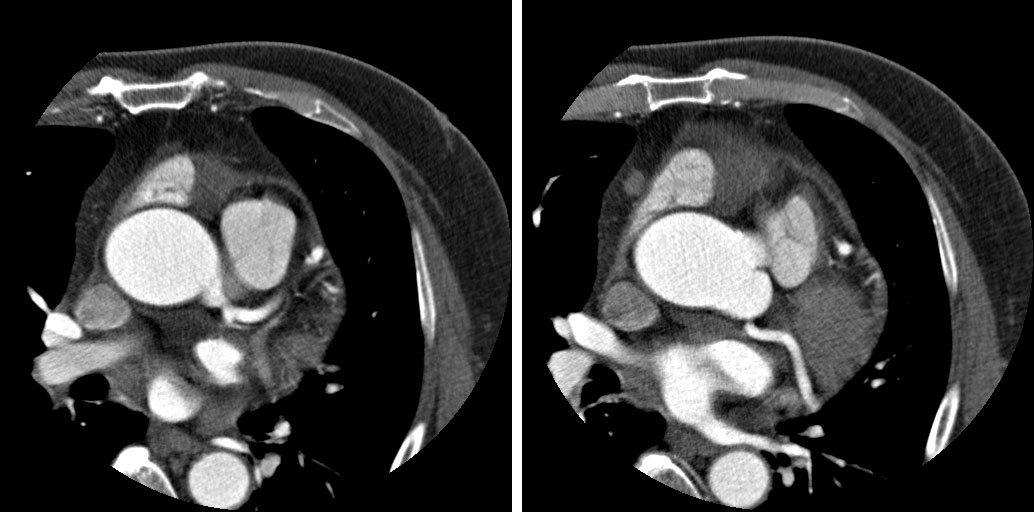

M/60 C.C. Atypical chest pain (since 2months) / Diabetes + / HR at MDCT scan: 70-75 bpm.

CHARY DURAIKANNU, VRR Diagnostics, INDIA

HIT : 82